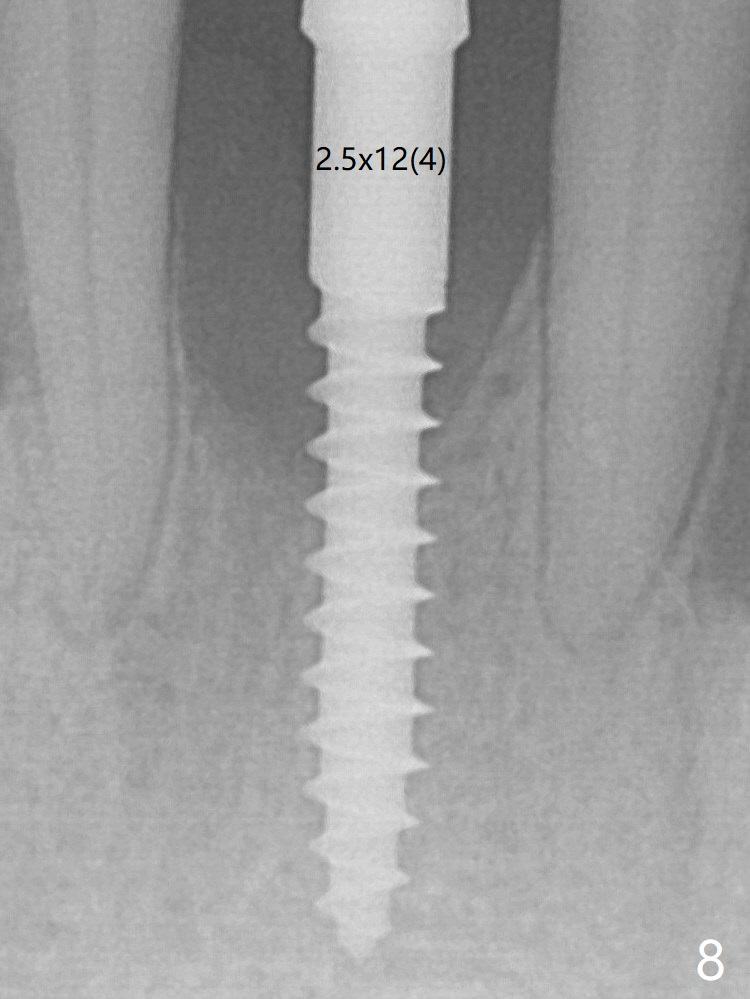

Because of the narrow flat ridge buccolingually, a 2.5x12(4) mm 1-piece implant is placed with >40 Ncm (Fig.8). With deeper placement of the implant, Vanilla graft is placed in 2 steps (Fig.9,10 *). No implant threads are exposed 10 months postop (Fig.11).